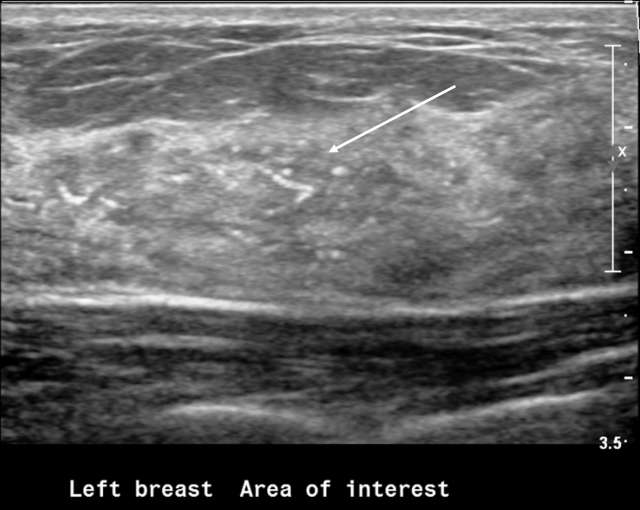

Outside of a mass, calcifications are generally harder to visualize as they may blend in with the hyperechoic speckles in the breast and Cooper ligaments. However, when an abnormal nonmass sonographic finding is identified (defined as a “discrete identifiable area of altered echotexture compared with that of the surrounding breast tissue that does not conform to a mass shape”) and demonstrates associated calcifications, such findings are frequently associated with malignancy3. Studies have shown that calcifications are present in up to 51% of malignant nonmass findings compared to 0-10% in benign nonmass findings3.